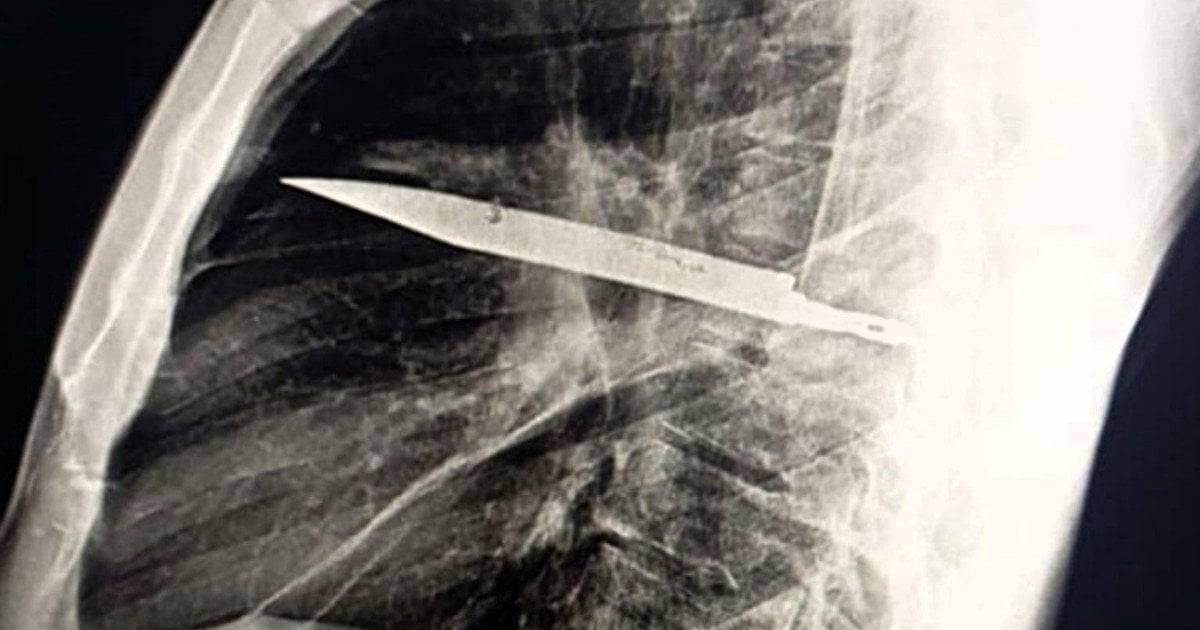

Обмін полоненими 14 серпня

Обмін полоненими 14 серпня / © Координаційний штаб з питань поводження з військовополоненими